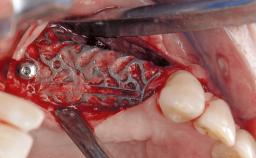

Reconstructive Surgical Treatment of Peri-Implantitis with Long-Term Follow-up

A 72-year-old female patient was referred to the specialist clinic with signs of peri-implantitis associated with implant 14. Two implants (sites 14 and 15) had been in function for three years. The patient was in good general health and was not taking any medication. She was a former smoker (12–15 cigarettes a day for 50 years) but had ceased smoking two years prior to implant placement. Her periodontal condition was stable, with no probing depths above 5 mm and a full-mouth plaque score (FMPS) of 35%.